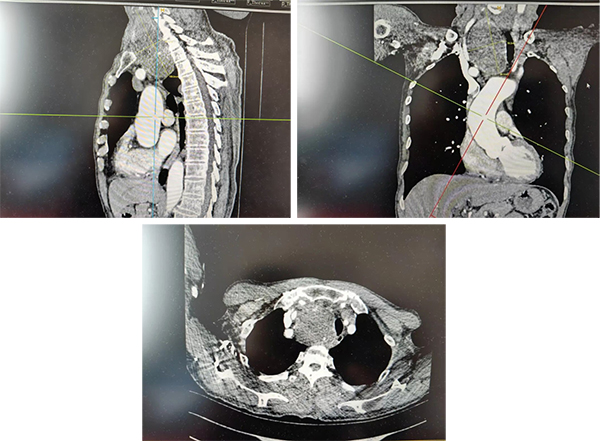

据悉,患者就诊时,甲状腺右侧叶已长出一枚巨大肿物。检查显示,该肿物最大直径约10cm,且大部分降入胸骨后,位置极深,解剖结构复杂给治疗带来极大挑战。更棘手的是,长期受巨大肿物压迫,患者气管严重左偏,呼吸功能明显受损;若不及时手术干预,肿物持续增大可能进一步压迫大血管、神经等重要组织,随时可能危及生命。然而,颈胸交接区域血管神经密集,胸膜顶结构复杂,加之肿物体积巨大、位置特殊,常规手术入路难以触及病灶,手术难度极高、风险极大,对手术团队的技术水平和协作度提出了严峻考验。

随后,普外科第二病区负责人李泽强团队接力上阵,经颈部切口精准操作,在充分保护周围血管和神经的前提下,顺利将这枚直径约10cm的巨大肿物完整切除。整个手术过程有条不紊、衔接流畅,各团队配合默契,最终圆满完成手术,术中出血量少,未出现任何并发症。